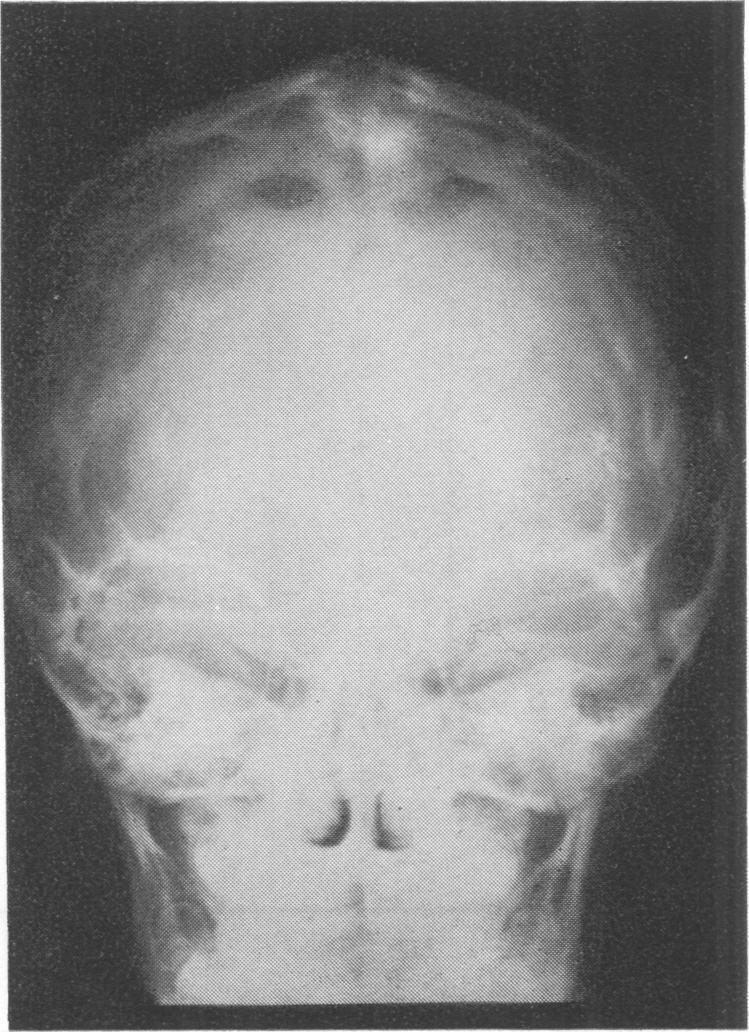

A 5-year-old boy and his father with Pfeiffer syndrome are described. They had acrocephaly, hypertelorism, antimongoloid slant of the palpebral fissures, protrusion of the eyes, large and broad nose, small mandible, irregularly placed teeth, additional upper canine, high-arched palate, partial syndactyly of fingers and toes, brachydactyly of toes, valgus deformity of hypertrophied triangular great toes, broad phalanges of the great toes and broad first metatarsals, accessory epiphyses lateral to the interphalangeal joint of the great toes, and normal intelligence. To our knowledge, this is the first family in which the syndrome is almost totally confined to the head and feet--it spares the upper limbs except for partial skin syndactyly between the fingers--and the third family showing inheritance through three successive generations suggesting an autosomal dominant mode of inheritance. The published papers are reviewed and the clinical and x-ray signs are tabulated.

本文描述了一名患有 Pfeiffer 综合征的 5 岁男孩及其父亲。他们有尖头畸形、眼距过宽、睑裂反蒙古样倾斜、眼球突出、大而宽的鼻子、小下颌、牙齿排列不规则、额外的上尖牙、高拱腭、手指和脚趾部分并指(趾)、脚趾短指畸形、肥大的三角形拇趾外翻畸形、拇趾宽趾骨和宽第一跖骨、拇趾指间关节外侧的副骨骺,且智力正常。据我们所知,这是第一个该综合征几乎完全局限于头部和足部的家系——除手指间部分皮肤并指外,上肢未受累——也是第三个显示连续三代遗传的家系,提示为常染色体显性遗传模式。对已发表的论文进行了综述,并将临床和 X 线征象制成表格。